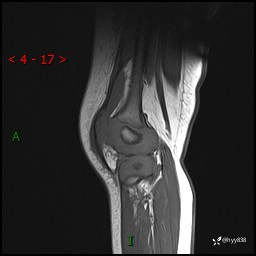

现病史:患儿1月前无明显诱因出现左下肢跛行,伴左膝关节红肿,无发热、咳嗽、恶心、呕吐等症,于当地医院就诊行X线片未提示异常,今至我院门诊就诊,门诊医师拟“跛行待查”收入院。 病后,患儿精神、食欲可,睡眠欠安,大小便通畅,体力体重无明显下降。

左膝MRI平扫